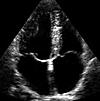

Диагностическая значимость эхокардиографии чрезвычайно высока. Как высокоинформативная, неинвазивная методика, эхокардиография используется для выявления сердечных изменений, которые не проявляются клинически и не обнаруживаются электрокардиограммой. Эхокардиография выполняется на специальных эхокардиографах, оснащенных ультразвуковым генератором от 1 до 10 МГц, датчиком, который обнаруживает отраженные ультразвуковые сигналы, ультразвуковым вибрационным преобразователем для электромагнитных волн и ультразвуковым преобразователем. записывающее устройство, отображающее изученные структуры сердца в виде эхокардиограммы. Современные эхокардиографы имеют электрокардиографический канал для одновременной записи ЭКГ и синхронизируются с компьютером для быстрой обработки и получения высококачественных данных.

В кардиологии одномерная эхокардиография используется в режимах отображения эха A, M и в; двумерная эхокардиография, а также допплеровская эхокардиография. Контрастная эхокардиография, контрастное эхо, чреспищеводная эхокардиография, стрессовая эхокардиография используются в качестве модификаций трансторической локальной ультразвуковой кардиографии. Стоимость эхокардиографии зависит от типа и метода исследования, класса эхокардиографического устройства. Для эхокардиографии требуются результаты последней ЭКГ, ранее выполненной эхокардиографии, 24-часовой мониторинг ЭКГ и АД (при наличии).